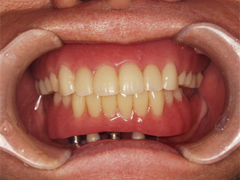

写真(1)口内写真

上下ともに歯がなく入れ歯を使用しているため顎の骨が溶けてしまい歯茎が下がってしまっている。

手術したその日からまともに食事ができるように手術したその日に仮の歯を入れました。

下顎インプラント(オールオン4),上顎総義歯